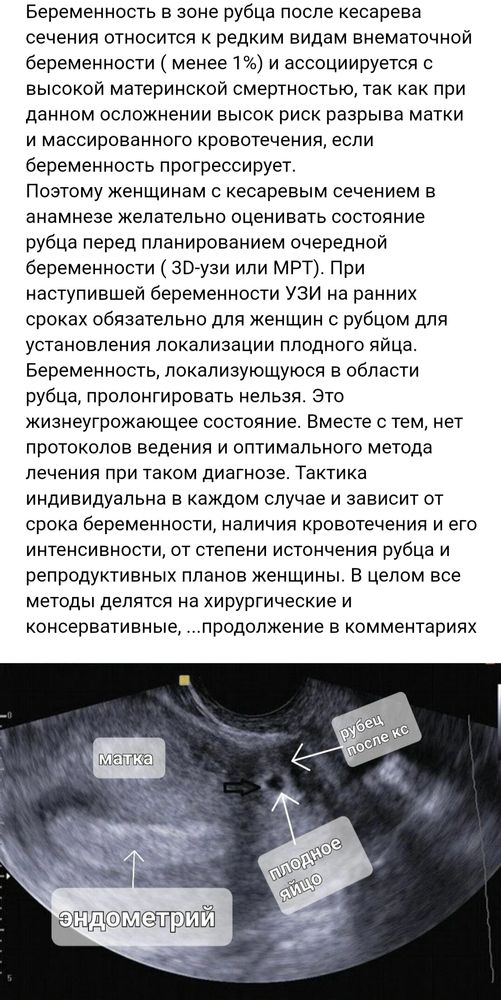

На узи в 5 нед 2 дня пя не нашли, но обнаружили нишу в рубце, которой никогда не было, тут закрались сомнения. В 5 нед 4 дня пошла в мёд центр, ПЯ обнаружили, но в нижнем маточном сегменте в области рубца) у меня 3 КС) узист вобще написала заключение - "эктопическая беременность в области рубца? '😞 Кто сталкивался? Чем закончилось? Я